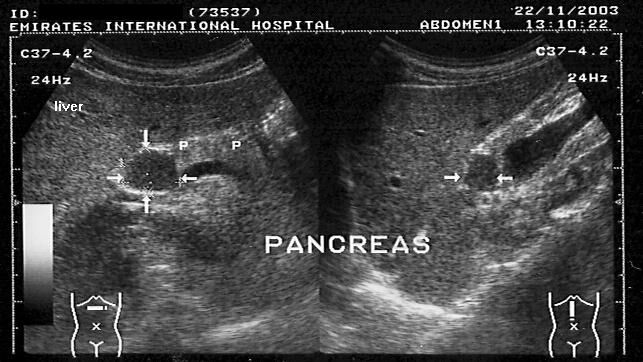

This patient presented with abdominal discomfort and underwent sonography of the abdomen. Ultrasound images show a rounded mass in the region of the pancreatic head and isthmus. It shows the same echogenicity as the liver (photos 1 and 2). This suggested the possibility of a pancreatic mass, possibly malignant.

However, images 3 and 4, reveal a different diagnosis- the possible "mass" appears to be an extension of the caudate lobe of the liver. These ultrasound images are diagnostic of "papillary process of the caudate lobe of liver."This normal variant may thus mimic pancreatic or preaortic lymph node masses.